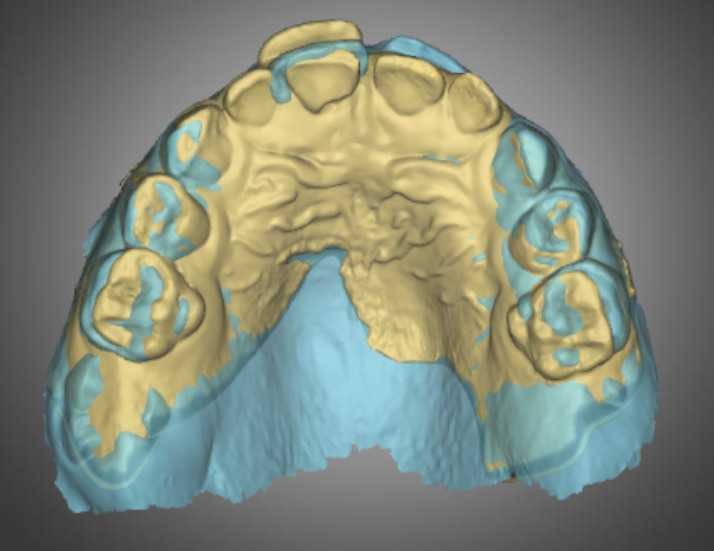

1st Review – 2023-03-01

- YELLOW = Initial 2022-10-29

- BLUE = 1st Review 2023-03-01

Great compliance in the first quarter. Evidence of arch expansion at the molar level.

2nd Review–2023-05-30

- YELLOW = Initial 2022-10-29

- BLUE = 2nd Review2023-05-30

Expansion maintained. Note eruption of the 16